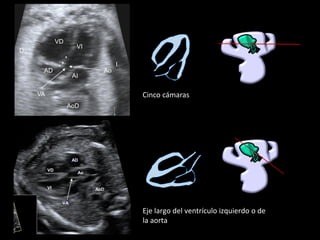

5C

Cinco cámaras

Desplazamiento paralelo delsde

el plano de cuato cámaras en

sentido cefálico

Eje largo del ventrículo izquierdo o de

la aorta

▪ Ao sale de VI

▪ Se continúa con el

septo IV